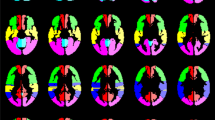

The MRI data preprocessing was performed using Statistical Parameter Mapping (SPM12) (https://www.fil.ion.ucl.ac.uk/spm/) running on MATLAB (R2018b (The MathWorks, Inc., Natick, Massachusetts; http://www.mathworks.com)). The DICOM images were converted to analyze format in NIfTI (Neuroimaging Informatics Technology Initiative), slice-timing corrected to equalize the time of image acquisition, realigned to correct subjects’ head movement, normalized to standard MNI space, spatially smoothed by a Gaussian kernel of 12-mm FWHM, and temporally interpolated by a factor of 4, resulting in a temporal resolution of 0.75 s. The mean CVR within vascular territories was analyzed by using a template in MNI space with 12 predefined volumes of interest (VOI) based on the arterial transit time flow territories [33, 34] (see Fig. 1). All further data processing was performed by use of in-house scripts programmed in MATLAB.

Volumes of interest based on the vascular territories of the anterior cerebral artery (red), the middle cerebral artery (frontal (green), temporal (yellow), and parietal (blue)), the posterior cerebral artery (pink), and the cerebellum (turquoise) separated by side [17]

The first step was to verify patients’ compliance in performing the breath-hold paradigm. We used an approach proposed by Hauser et al. [7] and recently applied [17, 19]: we utilized the above-mentioned predefined VOI of the cerebellum [33, 34] (see Fig. 1) to calculate the mean cerebellar signal time-course. The cerebellum is supplied by vertebrobasilar arteries that are unaffected by MMD and represents a region where a physiological hemodynamic response is expected [7, 17, 18, 35]. If the cerebellar signal time-course revealed no expected BOLD signal peak in visual inspection, we assumed a lack of compliance and excluded the bh-fMRI data set from the further analysis.